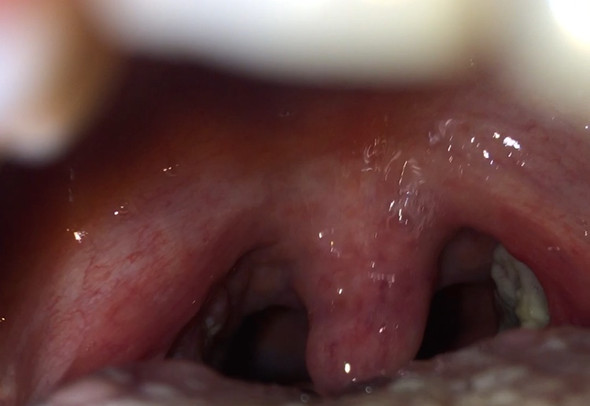

Weißer belag auf mandeln. Entzündung der Mandeln ja oder Nein. Diese Ausscheidung der Mandeln tritt als weißlicher Belag auf und wird vom Laien oft fälschlicher Weise als Mandelentzündung interpretiert. Ebenso gilt dies bei der akuten Mandel- und Rachenentzündung.

Weißer Belag auf den Mandeln ist ein Anzeigen dafür dass sich Eiter gebildet hat. Weißer belag auf mandeln. Bei einem massiven Angriff von Mikroben auf die Mandeln eines Kindes oder Erwachsenen auf den Körper kann ein gelblicher oder weißer Belag auftreten.

Häufig treten belegte Mandeln in Verbindung mit Schmerzen und Fieber auf. Ohne andere Symptome wie Rötung Halsschmerzen und Fieber liegt aber keine Entzündung vor. In den Mandeln bestehen demnach genau aus diesem gerade aufgezählten Gemisch.

Weiße Beläge auf den Mandeln entstehen durch Ablagerung von Speiseresten Schleim Zellabfällen oder Eiter in den Furchen der Gaumenmandeln. Hallo ich habe bei meinem Sohn 7 Jahre vor 3 12 Wochen weiße Beläge auf den Mandeln entdeckt er hatte aber weder Halsschmerzen noch Fieber. Mandelsteine Tonsillensteine sind weiß-gelbliche Gebilde die aus verschiedenen Substanzen in den Gaumenmandeln entstehen.

Weißliche Beläge bei Mandel- und Racheninfektion Tonsillopharyngitis Strenge Indikationsstellung für Antibiotika. Doch auch wenn zusätzliche Krankheitssymptome fehlen kann lästiges Fremdkörpergefühl oder unangenehmer Mundgeruch die Betroffenen. Man geht davon aus dass sie in manchen Fällen durch Halsschmerzen hervorgerufen werden.

Sie sind wenige Millimeter groß von meist fester oder krümeliger Konsistenz und können Mundgeruch verursachen.

Weißer belag auf mandeln. Weiße Punkte unter Nägel für eine Vielzahl von Gründen einschließlich Umweltschutzgründen oder Verletzung des Nagel angezeigt. Bei einem massiven Angriff von Mikroben auf die Mandeln eines Kindes oder Erwachsenen auf den Körper kann ein gelblicher oder weißer Belag auftreten. Hauptursachen sind Speisereste Schleim und Bakterien die sich in den Vertiefungen der Mandeln einlagern. Ansonsten sind Mandelsteine harmlos nur selten führen größere Exemplare zu weiteren Beschwerden. Ebenso gilt dies bei der akuten Mandel- und Rachenentzündung. Weiße Flecken auf den Mandeln. Das sieht zwar ein wenig unappetitlich aus ist aber meist ungefährlich und gehört zum Arbeitsprozess. Mandelsteine bestehen nur zu etwa einem Prozent aus Essensresten zu 99 Prozent handelt es sich um weiße abgeschilferte Epithelzellen und.

Entzündung der Mandeln ja oder Nein. Es bilden sich diese weißen Stippen die man Tonsillensteine nennt. Ohne andere Symptome wie Rötung Halsschmerzen und Fieber liegt aber keine Entzündung vor. Die weißen Stellen sind Absonderungen die beim Zersetzen der Nahrung und Bakterien entstehen. Werden sie von den. Bin aber trotzdem zum HNO dieser war nicht da aber eine Vertretung er sagte das ist nichts schlimmes es ist kein Eiter. Diese Ausscheidung der Mandeln tritt als weißlicher Belag auf und wird vom Laien oft fälschlicher Weise als Mandelentzündung interpretiert.